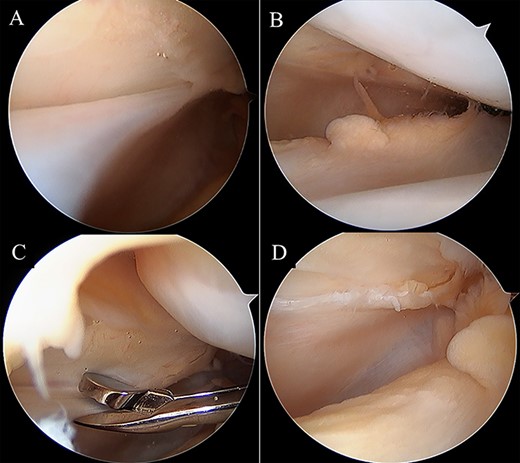

Intraoperative arthroscopic views. Medial synovial plica with a tight and hypertrophic margin (A). No injury to the patellar and femoral cartilage was observed (B). The synovial plica was partially removed with oval forceps (C). Image after removal (D).

Two months postoperatively, the patient presented with the pain in the medial margin of the patella during walking and knee extension, and the pain continued when she was allowed to start rhythmic gymnastics at 6 months postoperatively. There was no evidence of swelling, crepitus and ROM restriction, and her apprehension sign was also negative. Pain was relieved by an intra-articular xylocaine injection. Postoperative MRI showed no clear injury to the cartilage of the medial PF joint, and the medial PF joint space and the size of the medial plica were almost the same as before surgery (Fig. 2). Based on these findings, left medial plica syndrome was suspected. Although the patient underwent conservative treatment consisting of analgesics and physiotherapy, there were no signs of improvement, and consent was obtained for undergoing arthroscopic surgery at 8 months after the initial surgery. Intraoperative arthroscopic findings with probing confirmed an unenlarged but hardened and thickened medial plica (Fig. 3). No injury to the patellar and femoral cartilage was observed. The synovial plica was considered the main cause of pain, and we performed a partial resection of the medial synovial plica. The pain and the tenderness at the medial margin of the patellar during walking and exercising had gradually improved after surgery. The Lysholm scale improved from 85 to 100 points. At 2 years postoperatively, the patient has currently no pain in the medial side of the patella, negative apprehension sign. She has returned to play in rhythmic gymnastics.